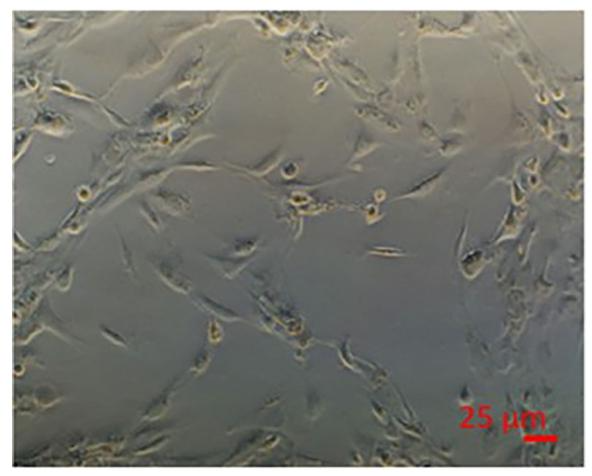

图 3:肝细胞与 NPCs 共培养的自组装结构

该图展示共培养体系的细胞排列:肝细胞与 NPCs 接种后,可自主组装为类似体内肝脏的结构化布局(structured arrangements),而非随机分布。这种自组装依赖细胞间信号互作(如 NPCs 分泌的细胞因子调控肝细胞极性),是模型能复现体内代谢功能的核心前提。研究指出,若细胞未形成该结构,可能导致葡萄糖 - 甘油三酯动态平衡异常,需调整培养基中脂肪酸浓度或细胞接种比例。